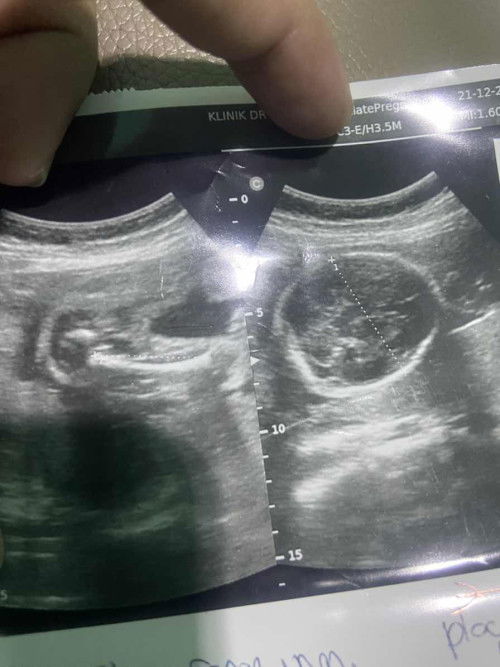

Assalamualaikum ibu2... maw tanya ada sapa2 yg taw jantina scan dlm gambar ni ?? kmarin dlu g scan klinik swasta doktor kata baby girl☺️.. harap2 btul lh sbb sblum ni dh ada boy... so sapa2 yg pernah scan mcm gmbr di bawah... komen sikit yaa ibu2

babygirl ni mcm saya 🩷

mcm babygirl je

harap2 lh wak dpt girl... doakan sy smoga dpt baby girl yaa🤲🏻 sbb sblum ni dh ada boy